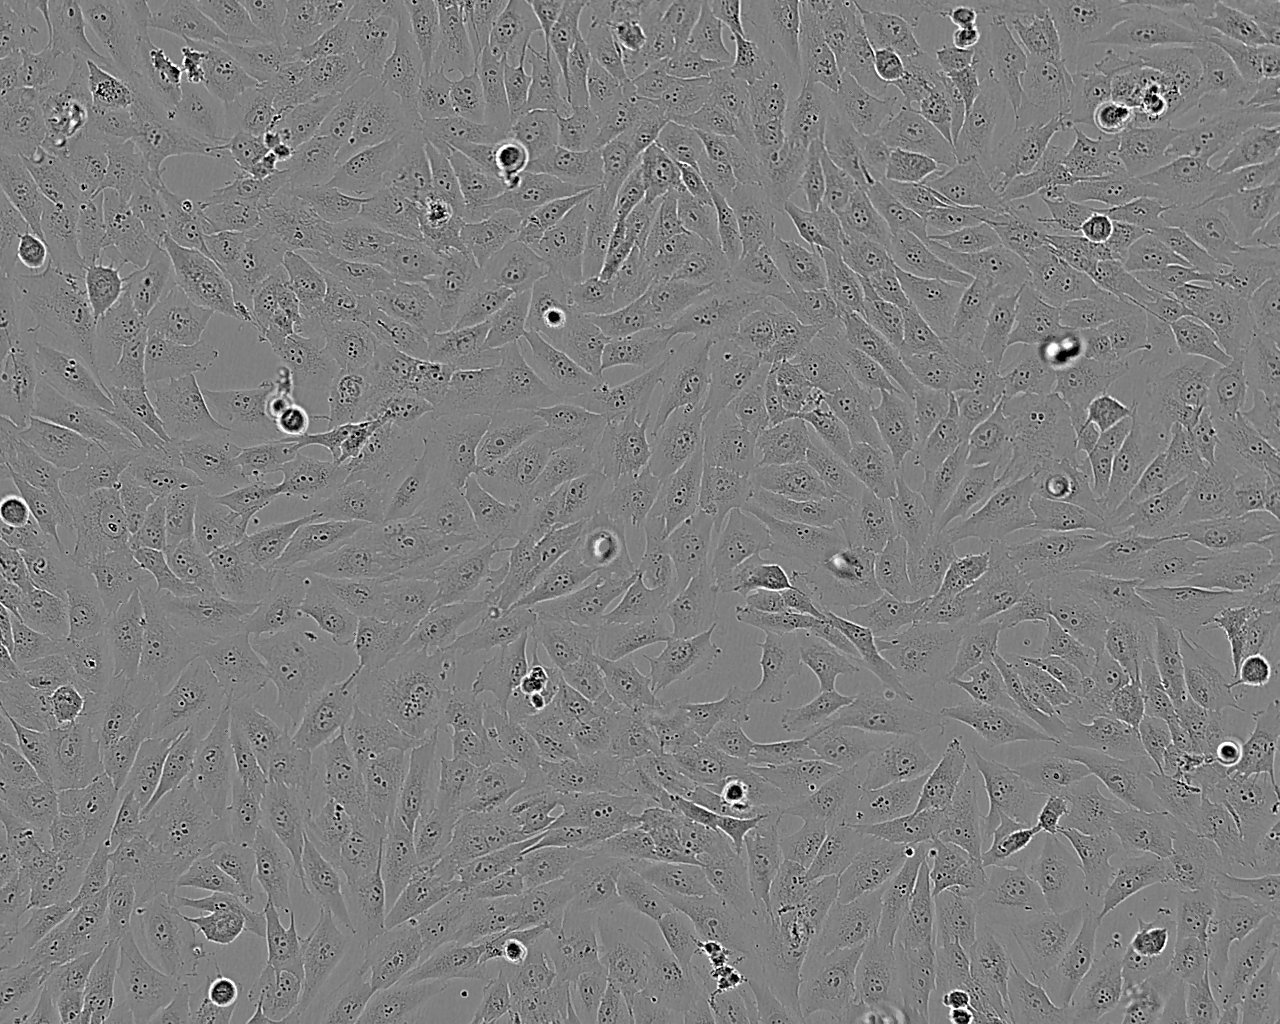

形态特征 上皮细胞样

生长特征 贴壁